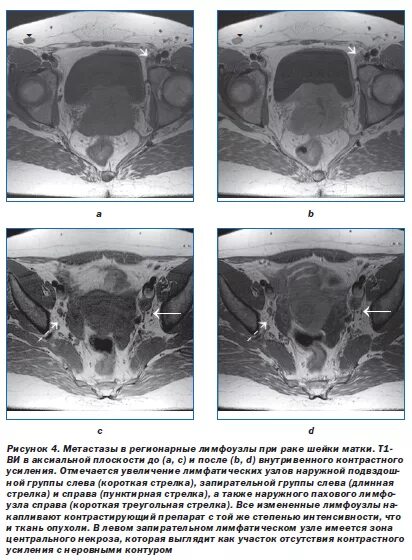

Метастазы рака шейки